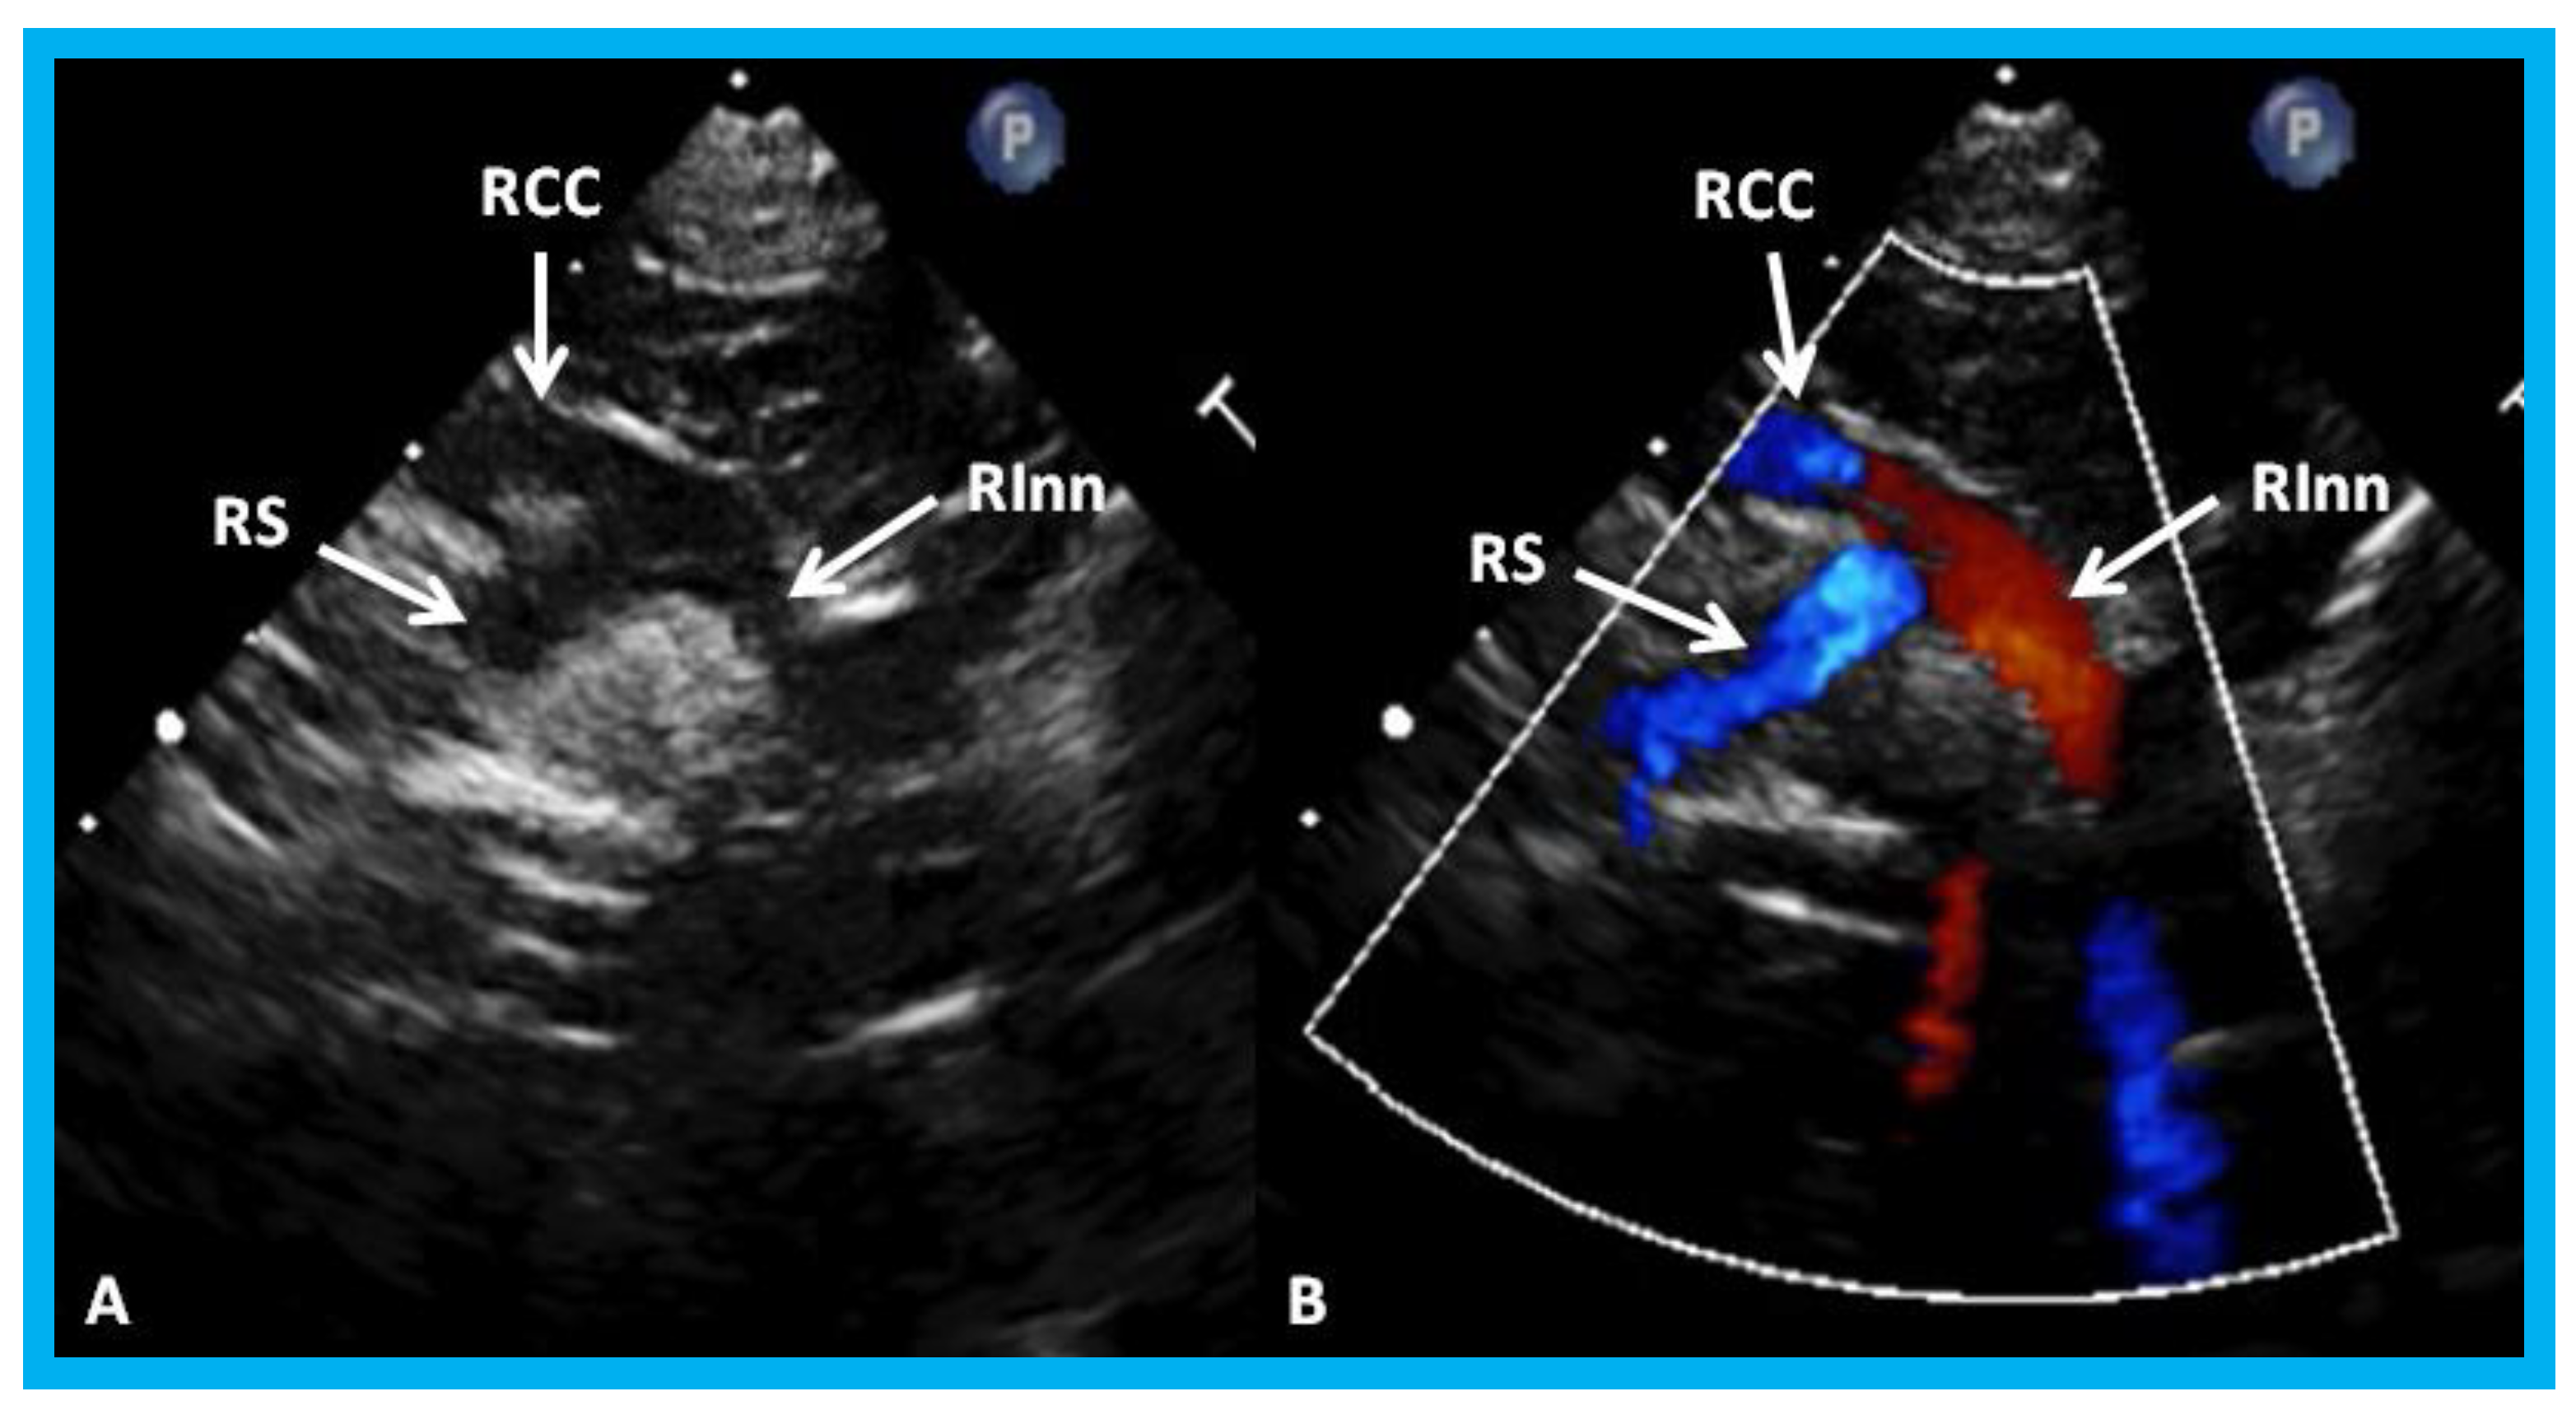

Figure 28. High parasternal views of the right innominate (RInn) artery demonstrating its division into right common carotid (RCC) artery and right subclavian (RS) artery by 2D (A) and color flow imaging (B): These data suggest left aortic arch.